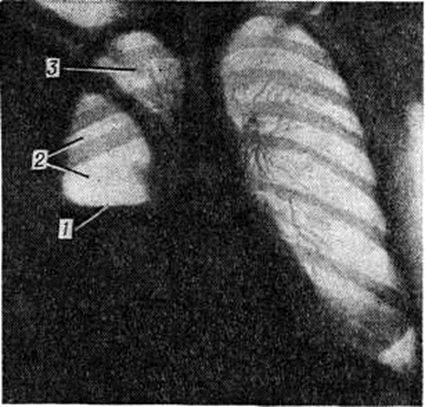

Острое развитие Пиопневмоторакс может обусловить появление симптомов острого живота (напряжение мышц передней брюшной стенки, симптом Щеткина—Блюмберга). При перкуссии лёгких на стороне поражения появляется коробочный звук, при аускультации — ослабление дыхательных шумов, иногда ослабленное бронхиальное дыхание с амфорическим оттенком. При тотальном Пиопневмоторакс с относительно небольшим количеством жидкого гноя иногда возможно определение шума плеска, описанного Гиппократом (смотри полный свод знаний Гиппократа шум плеска). Рентгенологически над горизонтальным уровнем жидкости в плевральной полости виден воздушный пузырь (рисунок 2).

Рис. 2.

Прямая рентгенограмма грудной клетки при правостороннем пиопневмотораксе: 1 — уровень жидкости, 2 — воздушный пузырь, 3 — лёгкое. Изменения в организме при Пиопневмоторакс вызваны, с одной стороны, нагноением, резорбцией продуктов жизнедеятельности микроорганизмов и распада тканей. Эти факторы обусловливают развитие гнойно-резорбтивной лихорадки (смотри полный свод знаний) или истощения, а в некоторых случаях явления тяжёлой интоксикации с признаками шока (смотри полный свод знаний). С другой стороны, при выраженном накоплении жидкости и газа в плевральной полости возможны расстройства кровообращения и дыхания, характерные для массивного закрытого или же клапанного пневмоторакса (смотри полный свод знаний).